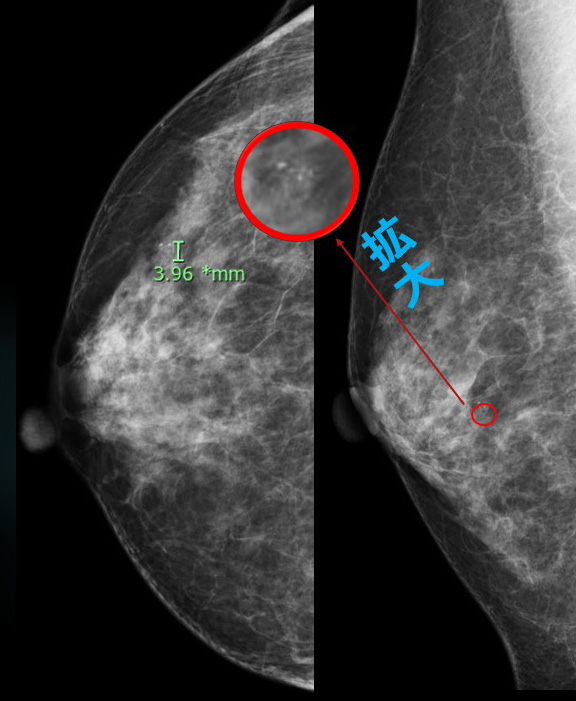

集簇した石灰化が区域性に並びカテゴリーⅤ(Ⅳ)

エコーでは、(石灰化に相当する部位に一致して)複数の「石灰化を含むlow echo」が認識できます。

★エコーで確認できるので(ST-MMTするまでもなく)、初診日にそのままMMTE施行しました。

石灰化がエコーで「どう見えるか?」

本来石灰化は「マンモグラフィーで見るもの」なので、「シコリ」のように「誰が見ても同じ所見」とはならない最たるものと言える。

石灰化がエコーで見える(見えた!)と思えるのは「点状のキラキラ」なんだけど…

実際には「正常乳腺構造も時に、点状キラキラ」に見えることがあるんだ。

今回のように予めマンモグラフィーで石灰化所見がある。さぁ、エコーで捉えるぞ!となった場合